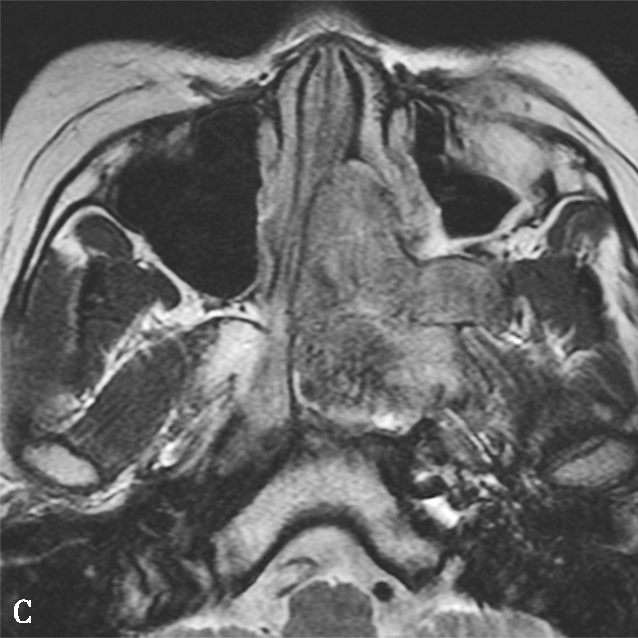

图1-2-4 青少年鼻咽纤维血管瘤

患者男,12岁,间断鼻出血1年。A.鼻窦CT横断面骨窗,示左侧蝶腭孔扩大,被不规则软组织肿块占据,病变累及左侧鼻腔、鼻咽、翼腭窝,邻近骨质可见溶骨性骨质破坏;B.鼻窦CT冠状面重组骨窗,示病变累及鼻腔、蝶窦,邻近骨质可见溶骨性骨质破坏;C.鼻咽部MR T 2 WI横断面,示左侧鼻咽、鼻腔不均匀等信号肿块,病变通过扩大蝶腭孔累及翼腭窝,病变内可见多发血管流空信号;D.鼻咽部MR T 1 WI横断面,示病变呈不均匀低信号;E.鼻咽部MR T 1 WI横断面增强+脂肪抑制序列横断面,示病变显著不均匀信号,与邻近组织分界尚清